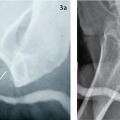

L’urétrocystographie rétrograde et permictionnelle (UCRM), indispensable, précise la localisation, la longueur et le nombre de sténoses. Opacification rétrograde de l’urètre et de la vessie par injection de produit de contraste au méat urétral, elle comprend une première série de clichés statiques et une seconde durant la vidange vésicale (fig. 2 et 3).2